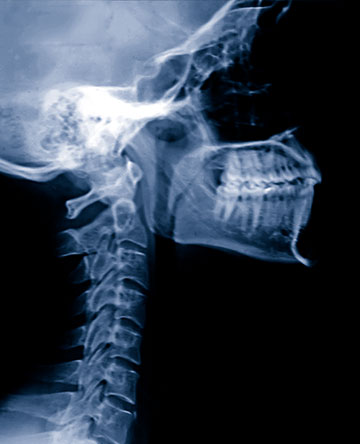

Wellington’s non-operative spine specialists provide effective conservative care for a wide range of spine problems using a comprehensive, multidimensional approach. Your Wellington spine specialist will perform a thorough evaluation, discuss the nature of your condition and review the available treatment options which may include medications, injections, bracing and exercise therapy. Most spinal problems respond to appropriate conservative care, but Wellington also works closely with many good local spine surgeons.